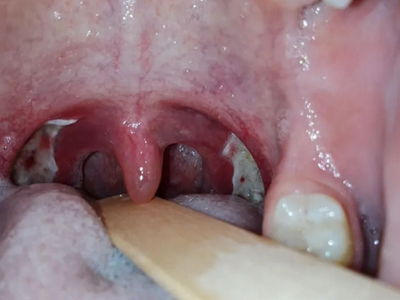

化脓性扁桃体炎扁桃体发红肿胀图

化脓性扁桃体炎患者口咽两侧的扁桃体充血发红,表面没有溃烂面,伴有咽痛,咽痛开始于一侧,继而双侧咽部均明显疼痛,吞咽时明显加剧。